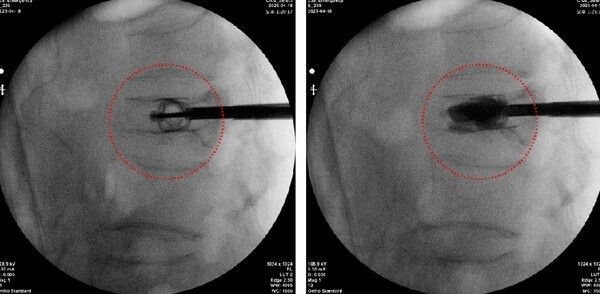

(스파인잭 티타늄 임플란트를 삽입해 척추압박골절 환자의 척추체를 정상에 복원한 모습, 국제바로병원제공)

[투어코리아=이창호 기자] 보건복지부 관절전문 국제바로병원은 척추 압박골절환자의 기존 척추체 풍선성형술 시멘트 삽입술보다 업그레이드된 최신 신의료기술 ‘경피적 척추 압박골절 보강술(일명 스파인잭)’을 사용해 지난 4월 초 70대 환자의 첫 시술을 인천 최초로 성공적으로 마쳤다고 전했다.

스파인잭(미국 Stryker사)시스템은 티타늄 임플란트를 이용한 경피적 척추체 보강술로 기존 척추 시멘트 시술 풍선성형술 이후 등이 굽거나 척추뼈가 무너지는 단점을 보완하게 되었다.

국제바로병원 이정준 병원장은 “티타늄 임플란트를 사용하는 스파인잭 시스템은 두개골 방향으로 확장시켜 척추체를 정상뼈에 맞게 척추압박골절 부위를 들어올릴 뿐 아니라 척추체에 분산되는 하중을 의료진의 숙련된 기술과 함께 받쳐줌으로써 시멘트 삽입을 통해 척추체 높이를 복원하는 신의료 기술이다. 이 기술은 60세 이상 뿐 아니라 고령환자의 척추압박골절 환자에게 기존 풍선성형술 이후 등이 굽거나 재골절되는 증상을 보완할 수 있는 확실한 치료법으로 자리매김 할 것으로 기대한다.”고 밝혔다.

척추압박골절은 x-ray와 단층화 촬영(CT)으로 먼저 진단을 하게 되는데, 척추관 협착증까지 동반한 경우 추가 MRI 정밀검사가 필요할 수도 있다. 이때 풍선성형술과 같이 한번에 풍선을 주입해 확장한 후 시멘트를 삽입하는 기존수술법보다 티타늄 임플란트를 통해서 단계적으로 의료진의 술기에 따라 척추체 확장이 가능해 환자의 해부학적인 원래의 척추뼈 모양대로 복원이 가능하고, 재골절율을 감소시킨다고 보고 되고 있다.

국제바로병원의 첫 수술을 성공적으로 마친 70대 초반 여성환자의 경우에도 지난 1월 빙판에 미끄러져 넘어진 후 척추압박골절이 발생되었고 보존적 치료에도 통증이 지속되어 내원하였다. 신의료기술인 스파인잭을 이용한 척추체 보강술을 시행하였으며, 척추체 높이가 정상에 맞게 복원되고 유지되므로 재발된 통증이 없어지고, 척추변형이 심한 경우 척추 후만증으로 무너져 상태가 추가로 악화되는 것을 예방 할 수 있게 되었다.